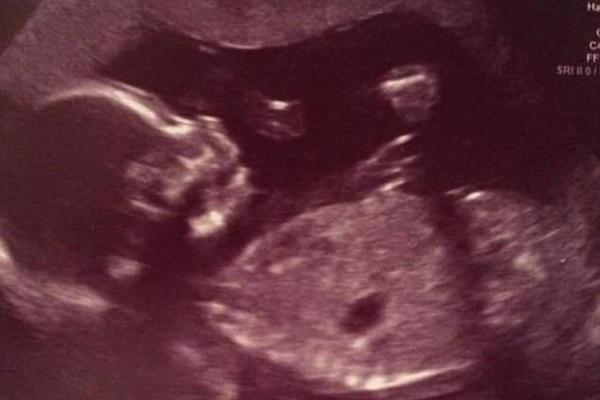

Сообщается, что беременность Джеммы протекала хорошо, пока на 36-й неделе не произошла скрытая отслойка плаценты. Тревожные симптомы проявились не сразу, а когда Джемма почувствовала сильную боль - ребенка уже было не спасти.